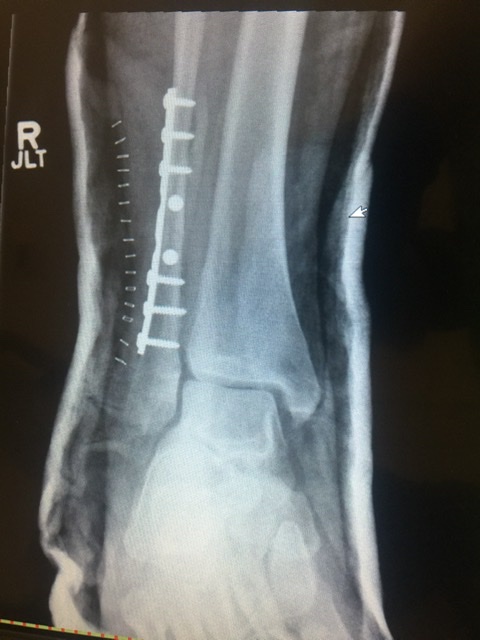

Well, it looks like my riding season is slightly curtailed for this year.

While riding out of Cawston I caught a large rut with the rear tire and the rear end swung out very quickly trapping my foot twisting it backwards. Luckily I was riding with Adrian, Erich, Randy and Bill. Thanks a lot guys for getting me out of there and getting my bike out safely. I’m looking at six weeks on crutches with no weight bearing. I’m likely done riding for the season.